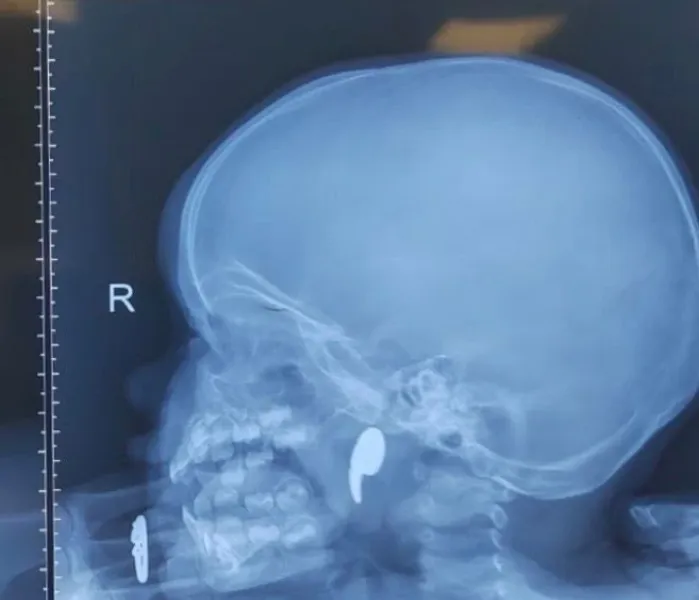

В городскую больницу №11 поступила женщина 1965 года рождения с жалобами на сильную боль в пояснице и ногах, онемение при ходьбе и резкое ограничение движений. Диагноз выявил множественные патологии позвоночника, включая поражение межпозвоночных дисков и стеноз позвоночного канала.

До этого пациентка в течение года проходила курсы консервативного лечения, но положительной динамики не было. В больнице ей предложили декомпрессивно-стабилизирующую операцию.

Хирурги выполнили микрохирургическое вмешательство: освободили спинной мозг от сдавления, удалили грыжу и заменили поврежденные диски имплантами. Также исправили смещение позвонка и установили стабилизирующую конструкцию из титановых винтов и балок.

Операцию провела бригада под руководством нейрохирурга Евгения Дронова. Послеоперационный период прошел без осложнений. На следующий день пациентка уже вставала и передвигалась без боли. Функции нервов восстановились за неделю, походка нормализовалась. На восьмой день женщину выписали под наблюдение невролога.